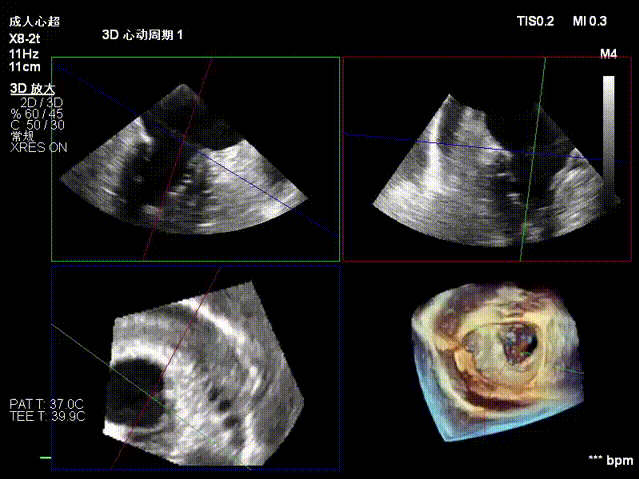

术前经食道超声显示:二尖瓣C1、P1区脱垂,重度关闭不全,彩色多普勒提示大量二尖瓣反流。术前瓣口面积MVA约5cm²,瓣环前后径AP约36.9mm,前叶A1约26mm,后叶P1约15.2mm。

术后即刻反流降为少量,剩余瓣口面积2.57cm²,平均跨瓣压差2mmHg。

术后复查超声心动图显示:二尖瓣轻度返流,三尖瓣中度返流,二尖瓣可见金属夹回声,启闭正常;各心室大小正常,升主动脉不宽,主瓣回声增强,启闭良好;二尖瓣舒张期峰值流速1.4 m/s,功能面积2.1 cm²,跨瓣平均压差约4 mmHg。